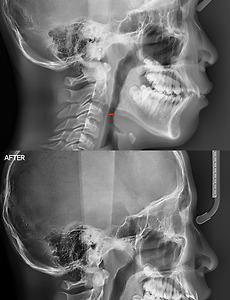

미소드림치과79 턱관절 안면비대칭 교정을 햐고 엇어염 ■ 미소드림 치과>턱관절/비대칭>비수술 교정 진료 지식 얼마전 대기실에서 사진을 찍고 있었습니다. 본원 홈페이지에 사진 사용을 허락한 남자 분을 찍어주고있던건데요. 갑자기 턱관절 안면비대칭 문ㄴ제로 검사와 상담을 받았던 어머님께서 "아! 홈페이지에서 본 분인다."이리 말씀을 하시면서 상태가 정말 좋아졌다며 엄지척을 해주셨습니다 ㅎㅎ 그래서 이번 포스팅은 턱관절 안면비대칭 교정을 하고 있어요 라는 한 문장을 증명해줄 경과 사진 입니다. 사진과 함께 왜 비대칭이 생겼던것인지를 알려드리는 지식글도 남겼습니다. 같은 증상으로 고민하는 분들께 조금의 도움이라도 되길 희망해봅니다. 감사합니다. 턱관절은 좌우 양측이 따로 운동하지 않습니다. 둘이 동시에 움직이는 협조 운동을 하는 관절로 회전운동외에 활주운동을 합니다.. 2018. 5. 30. 턱관절 안면비대칭이 나타나면 어떻게 해야하나?? 턱관절 안면비대칭..어떻게 해야하나요? 남들과 달리 내 얼굴을 거울 통해서 보면..혹은 사진을 찍어서 보면..좌우 대칭이 너무 맞지 않는다. 이건 안면비대칭이 확실하다 라고 생각되는 분들이 의외로 많습니다. 안면비대칭, 왜 나타난걸까요? 케바케 (요즘 줄인말로요 ㅎㅎ) 지만, 보통 턱관절이 틀어지면서 안면비대칭이 나타납니다. 턱관절 장애 및 틀어짐이 없을 때는 이렇게 교합평면이 수평을 이루게 됩니다. 그러나 턱관절 장애가 생기어 교합평면이 무너지게 되면, 아래 이미지와 같은 모습으로 변화합니다. 교합평면이 무너졌고, 안면비대칭 모습을 보여주게 됩니다.그럼 엑스레이 사진과 얼굴 정면 사진을 보면서 턱관절 안면비대칭 증상을 자세히 살펴보겠습니다. 턱관절 상태가 잘 보이는 엑스레이 사진인데요. 빨간 선으로 턱.. 2018. 5. 23. 턱관절 장애 자가진단 이렇게 해보자 - 강남 턱관절치료병원 강남역 미소드림치과턱관절치료병원, 티스토리 포스팅 턱관절 장애 자가진단 이렇게 해보자(자료출처:임상에서 쉽게 적용할 수 있는 턱관절 장애의 해법 / 3장 65페이지) (1) 상악 중정치(대문니)의 중심선과 아랫니 중절치의 중심선이 일치된 상태에서 입을 벌렸을 때 중심선이 똑바로 벌어지는가 확인해본다. 만약 입이 한쪽으로 돌아간다든지 지그재그로 입이 벌어지면 턱관절 디스크 및 주변 근육에 이상이 있는 것으로 볼 수 있다. (2) 두 손을 턱관절 부위에 올려놓고 입을 벌렸을 때 턱관절에서 소리가 나는지 확인한다. 만약 소리가 나면 턱관절 디스크에 이상이 생긴 것이다 (3) 두 손을 턱관절 부위에 올려놓고 입을 벌렸을 때 입을 크게 벌리는 순간 턱관절 부위에 불룩하게 올라오는 것이 만져지는가 확인한다. 만약 .. 2018. 5. 15. 거북목(일자목), 호흡장애가 턱관절 장애 때문이라고? 거북목(일자목)이 왜 생겼을까?알고보면 턱관절 장애 때문? 왜 숨쉬는게 버거울까?알고보니 호흡장애가 생긴게 턱관절 장애 때문? 이라는 글을 보시면 쉽게 이해가 되지 않을 것 같습니다.왜냐면 턱관절과...목,호흡..정말 연관없어보이니까요.그러나 분명 턱관절 장애로인해 이 두가지 문제(거북목 증상 및 호흡장애)가 발생하기 때문에, 이번 포스팅을 통해 하나의 의료지식 추가해가십시오 ^^ 모든 거북목(일자목)의 케이스가, 또 모든 호흡장애의 케이스가 턱관절 장애 때문은 아닙니다. 그러나 턱관절 장애로 아래턱이 과도하게 뒤로 밀려있다면, 치과를 내원하여 정확한 검사를 받아봐야 합니다. 과개교합 상태에서 교합간섭이 발생하면서 턱관절 장애가 생겼고, 아래턱이 뒤로 밀렸습니다. 이러한 이유로 수면 중 기도쪽이 압박을 .. 2018. 5. 15. 이전 1 2 3 4 5 ··· 20 다음